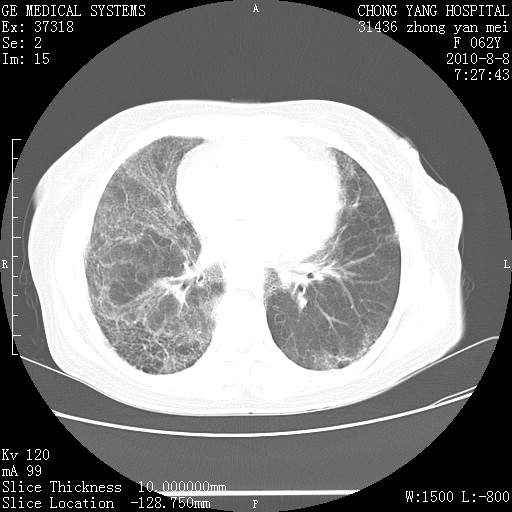

标题: CT28269:F62Y咳嗽胸痛数月。 [打印本页]

标题: CT28269:F62Y咳嗽胸痛数月。

两肺弥漫性间质纤维化伴继发性支扩。

考虑特发性肺间质纤维化

考虑两肺间质性肺炎并肺间质纤维化。

双肺间质纤维化合并感染、肺气肿

两肺间质纤维化并牵拉性细支气管扩张。

考虑两肺间质性肺炎并肺间质纤维化,肺气囊形成。

两肺间质改变,纵隔淋巴结肿大,需要考虑结节病的可能。